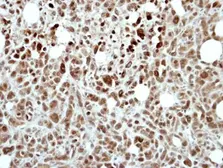

Product

Images

Description

Applications